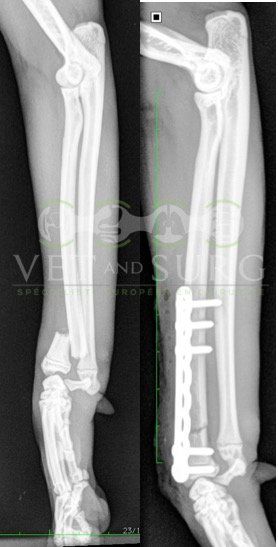

Fracture Salter-Harris sur un chaton Européen de 10 mois

Spike, chaton européen mâle de 10 mois, a été présenté en consultation pour boiterie du membre postérieur droit à la suite d'une chute depuis le 1er étage.

A la radiographie, une fracture de type Salter-harris 1 est diagnostiquée, avec déplacement de l'about discal.

Une réduction de la fracture par pose de 2 broches en croix a été réalisée.